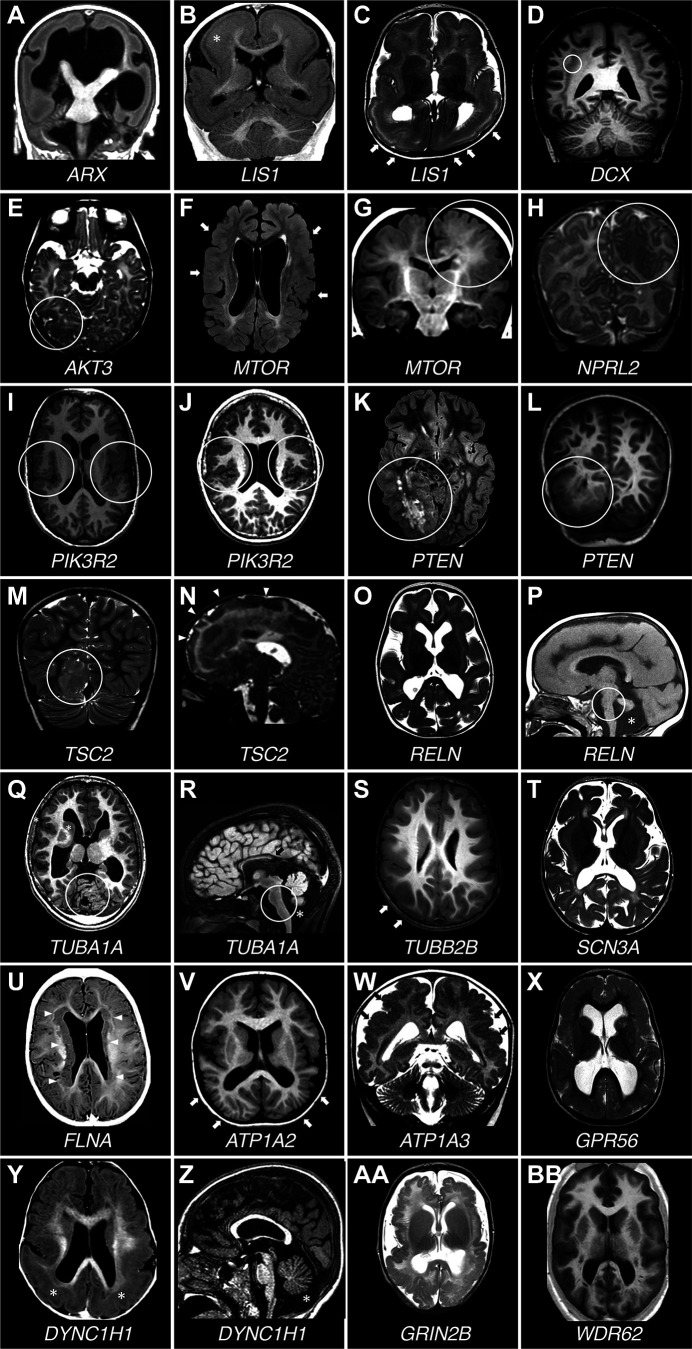

图 7.患有不同皮质发育畸形的患者的脑MRI。A : T1加权(T1W)冠状切面。一名患有ARX突变的男孩患有无脑畸形。脑室严重扩张,胼胝体缺失,基底神经节严重发育不全。B和C:患有后脑回>前脑回巨核细胞增生和皮质厚度增加的脑部的冠状T1W和轴位T2加权(T2W)切面。该男孩患有LIS1突变。B图中的白色星号表示皮质增厚较为严重的部位。C图中的白色箭头指向皮质更为光滑和厚实的区域。D : T1W冠状切面。一名患有DCX突变的女孩出现弥漫性皮质下带状异位。白色圆圈环绕着皮质下层状异位,该异位在皮质下方形成几乎连续的带状,由白质与其隔开。E :轴位T2W切面。一名女孩的右侧枕叶皮质发育不良(白色圆圈包围), AKT3基因存在极低水平镶嵌突变(脑内 0.67%,血液中未检测到)。F和G :2 名携带MTOR基因镶嵌突变且镶嵌率不同的患者的轴向液体衰减反转恢复 (FLAIR) 和冠状 T1W 切片(F:p.Thr1977Ile,血液中镶嵌率为 20%;G:p.Ser2215Phe,手术切除的发育不良脑组织中镶嵌率为 5.5%)。在F中,患者患有巨脑畸形,脑室较大,皮质多处异常区域交替出现内褶,表面光滑。这种模式提示多小脑回畸形(白色箭头)。G图中,白色圆圈突出显示皮质发育不良区域,脑实质体积增大,灰白质交界处模糊,皮质折叠不规则。H:T2W冠状切面。一名携带NPRL2突变的女孩的左侧顶颞叶局灶性皮质发育不良。圆圈围绕着皮质异常的顶叶部分。I和J:2名携带p.Gly373Arg PIK3R2基因突变且嵌合率不同的患者的T1W轴位切面( I :血液中嵌合率为13%,唾液中为43%;J :血液中嵌合率为10%,唾液中为29%)。两名患者均有双侧外侧裂周围多小脑回畸形(白色圆圈)。K和L:轴向 FLAIR 和冠状 T1W 切片显示患有体质性PTEN突变的男孩的右后象限发育不良(白色圆圈)。M和N:2 名患有体质性TSC2突变的患者的 T2W 冠状和矢状切片(M:p.Thr1623Ile;N:p.Pro1202His)显示由大型皮质结节(M,白色圆圈)引起的右后象限发育不良以及涉及大部分右额叶的广泛发育不良区域(N,白色箭头)。O和P :T2W 轴向和 T1W 矢状切片。患有RELN突变的女孩的平滑脑畸形,皮质厚度正常,小脑发育不全(P ,星号)。白色圆圈环绕着发育不全的脑干。Q和R :轴向和矢状 T1W 切片。一名携带TUBA1A突变的男孩,皮质增厚,脑回形态简化,小脑发育不全。圆圈环绕发育不全的小脑和脑干。星号表示发育不全的小脑蚓部下方区域,黑色箭头指向发育不全且缺乏最后部的胼胝体。S :T1W轴切面。一名携带TUBB2B突变的男孩,脑回形态弥漫性简化,侧裂明显增厚内翻。箭头指向皮质光滑区域。T :T2W轴切面。一名携带SCN3A突变的女孩,出现严重的脑回发育障碍,脑回形态简化。U :T1W轴切面。一名携带FLNA突变的女孩,出现典型的双侧脑室周围结节性异位。双侧室管膜下异位结节(白色箭头)连续,广泛覆盖于脑室壁。V :T1W 轴位切面。一名携带 ATP1A2 突变的男孩,脑内可见弥漫性多小脑回畸形,后部更为明显(白色箭头)。W : T2W冠状切面。一名携带ATP1A3突变的男孩,脑内可见多小脑回畸形,伴有异常皮质内褶和密集小脑回畸形(黑色箭头),并伴有异常脑沟。X :T2W 轴位切面。一名携带双等位基因GPR56突变的男孩,脑内可见双侧额顶叶皮质增厚和弥漫性异常皮质模式。Y和Z : T1W 轴位和矢状切面。一名携带DYNC1H1突变的女孩,脑回增厚和外侧裂周围多小脑回畸形。Y 轴位标有星号位于皮质增厚最严重的地方,即后皮质。Z 中的星号位于发育不全的小脑蚓部下方。AA : T2W 轴位。一名携带GRIN2B突变的男孩出现弥漫性多小脑回畸形。BB :T1W 轴位。皮质模式弥漫异常,皮质光滑,并有异常内褶区域,提示一名携带双等位基因 WDR62 突变的男孩患有多小脑回畸形。

在脑形态异常中,MCD 最常与复发性癫痫相关。在 MCD 中,一些细胞的发育过程发生改变,而这些细胞在正常情况下会参与正常大脑皮层形成,而癫痫发作可能由于神经元定位异常、增殖或分化异常或皮层组织异常而发生。

神经元错位是大脑发育过程中神经元迁移改变的结果。与神经元迁移缺陷相关的DEE的一个典型例子是由位于Xp21染色体上的无芒相关同源框( ARX )基因突变引起的,该基因突变可导致一系列几乎连续的神经发育障碍表型,包括伴有性别不明的无脑畸形(XLAG)(图7 A )、Proud综合征、Partington综合征、无脑畸形的婴儿痉挛症以及伴有癫痫的综合征性和非综合征性智力障碍。

ARX 蛋白属于配对 (Prd) 类同源域蛋白中与 Aristaless 相关的亚群。同源域转录因子在大脑发育和模式形成中起着至关重要的作用。具体而言,ARX 参与 GABA 能神经元的正常切向迁移,大多数携带该基因突变的患者发生癫痫发作可归因于此类神经元的错误定位或功能障碍以及抑制性神经传递的丧失。因此,ARX相关的发育性癫痫性脑病 (DEE) 被认为是一种“发育性中间神经元病”,该术语旨在将中间神经元的发育、迁移或功能受损引起的发育性脑疾病与中间神经元的功能缺陷或继发性丧失以及更常见的通道病区分开来。发育性中间神经元病还可能包括如上所述的 Dravet 综合征,以及由于PAFAH1B1 (也称为LIS1(图 7 B和C)或DCX(图 7 D))突变导致的经典型无脑畸形。PAFAH1B1基因编码胞浆 I 型血小板活化因子 (PAF) 乙酰水解酶的调节性 β 亚基,该亚基参与神经元间迁移和存活,而DCX编码对径向和非径向神经元间迁移到大脑皮层所必需的微管相关蛋白。在获得性发育性癫痫性脑病 (DEE) 模型中也有中间神经元病的描述,例如 ISS 的多重打击模型,尽管潜在的神经元间缺陷和机制可能不同,需要不同的针对性治疗方法。

MCD 的表型连续体包括局灶性皮质发育不良 II 型 (FCDII)、半巨脑畸形 (HME)、巨脑畸形 (MEG) 和发育不良性巨脑畸形 (DMEG),主要由 mTOR 通路基因的组成性和体细胞突变引起,即AKT1和AKT3(图 7 E)、DEPDC5和MTOR(图 7 F和 G)、NPRL2(图 7 H)、NPRL3、PIK3CA和PIK3R2(图 7 I和J)、PTEN(图 7 K和L)以及TSC1和TSC2(图 7 M和N),代表了由异常神经元增殖或分化以及异常神经元迁移引起的发育性癫痫性脑病 (DEE) 的范例。在因药物难治性癫痫而接受手术治疗的儿童中,近一半是由 FCD 引起的,粗略估计,在美国有近 40 万人(Wolters Kluwer UpToDate 网站,https://www.uptodate.com/contents/evaluation-and-management-of-drug-resistant-epilepsy)。除了皮质分层异常外,FCDII 还具有大的畸形神经元,这些神经元没有(IIa 型)球状细胞或有(IIb 型)球状细胞。HME 是一种一侧半球异常大于对侧半球的疾病,而 DMEG 是一种皮质发育不良与节段性脑过度生长有关的疾病,它们的组织病理学特征与 FCDII 相似。结节性硬化症 (TSC) 是一种先天性综合症,其特征是在包括大脑在内的多个器官中发展良性肿瘤 (错构瘤),并具有主要包括早发性癫痫、智力障碍和有时自闭症的神经系统表型,该综合症也是由肿瘤抑制基因TSC1或TSC2突变导致的 mTOR 通路失调引起的。